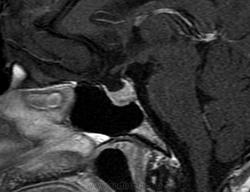

Ж, 37 лет. Наблюдается по поводу микроаденомы гипофиза, исследование в динамике. Предыдущие снимки сделаны в другом учреждении около года назад, картинка примерно такая же, однако на пленке отсроченные и постконтрастные снимки отсутствуют. В заключении была обозначена микроаденома округлой формы 3мм в диаметре.

Вот такая интересная картинка у нас получилась:

T1

T2

А, гипофиз, что, полупустой?

Не полупустой, в нижних отделах странной формы аденома. Плоская какая-то. За аденому то, что она хоть и медленно, но накапливает контраст, который в ней задерживается после того, как уже почти полностью вымылся из здоровой паренхимы аденогипофиза. Полупустой гипофиз (вернее полупустое турецкое седло, ещё вернее вторично "пустое" турецкое седло) получается после удаления аденомы. Или после самопроизвольного опорожнения кисты/кистозной аденомы гипофиза. 2 часа назд такое контролировал.

Честно говоря, я сначала подумал, что гипофиз как будто "висит" над дном турецкого седла, а под ним - жидкость. После контрастирования действительно - аденома.

Нет, оказалось, что это вовсе не жидкость, а по характеру накопления парамагнетика - аденома необычной формы и локализации.